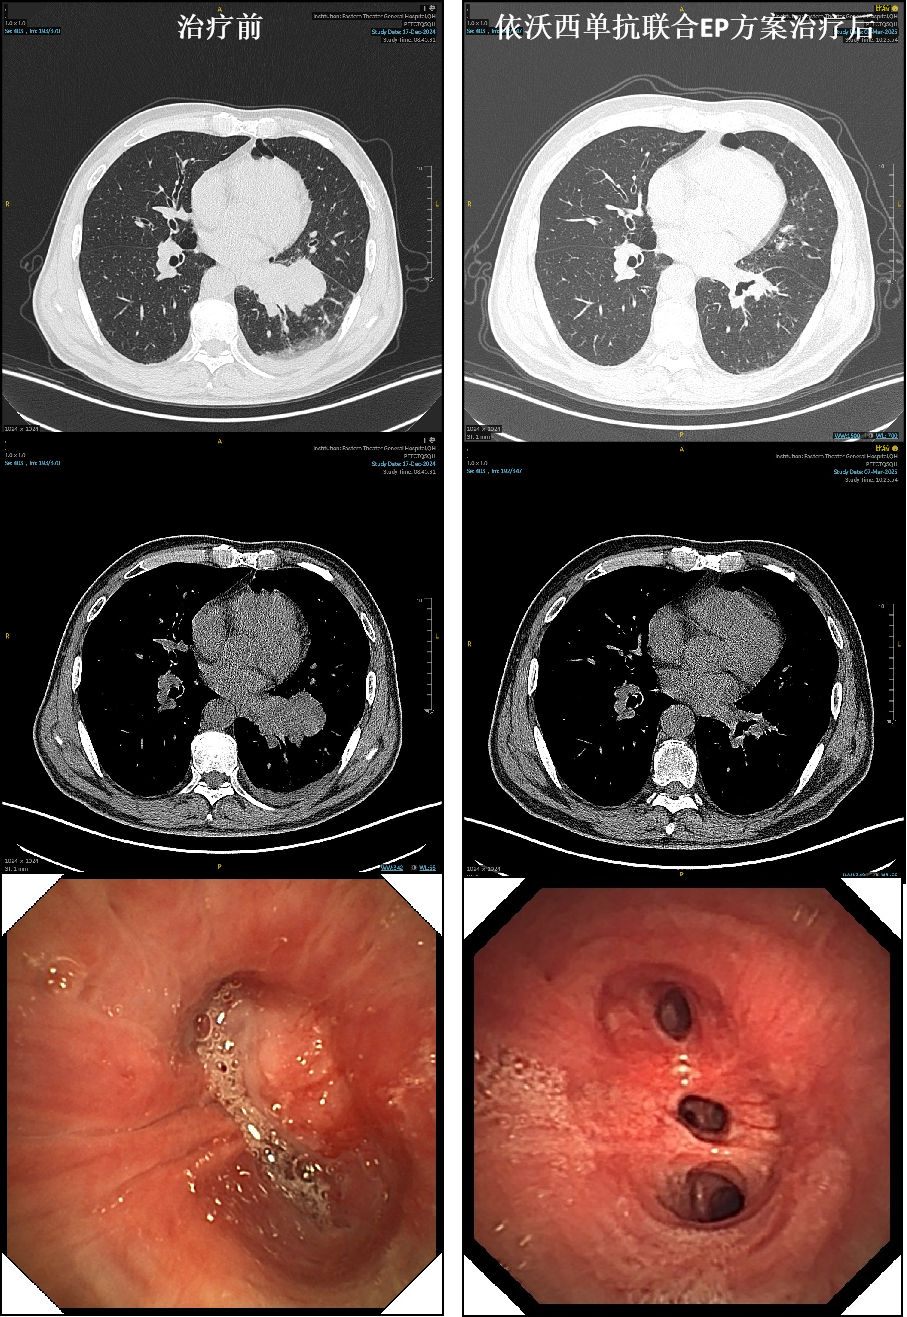

患者朱某(化名)因咳嗽就诊,经检查发现左下肺占位性病变,辗转至东部战区总医院秦淮院区呼吸与危重症医学科3病区住院,经过一系列全身检查及气管镜活检,确诊局限期小细胞肺癌!患者得知科室此项新型抗肿瘤药物的新型治疗模式下的临床研究,知情后入组了该项临床研究。经3周期依沃西单抗+依托泊苷+卡铂治疗,复查胸部CT显示病灶近乎消失,且气管镜下肿瘤显著退缩(见下图胸部CT及气管镜下表现)。

经多学科团队讨论后,心胸外科强勇主任医师团队成功为朱某进行了腔镜微创手术切除病灶。更让人欣喜的是,术后病理检查显示,肿瘤完全消失了(见下图的病理结果),这就是医学上说的pCR(病理完全缓解)。根据研究方案后续继续完成依沃西单抗联合依托泊苷和卡铂1疗程,后续运用依沃西单抗维持治疗。